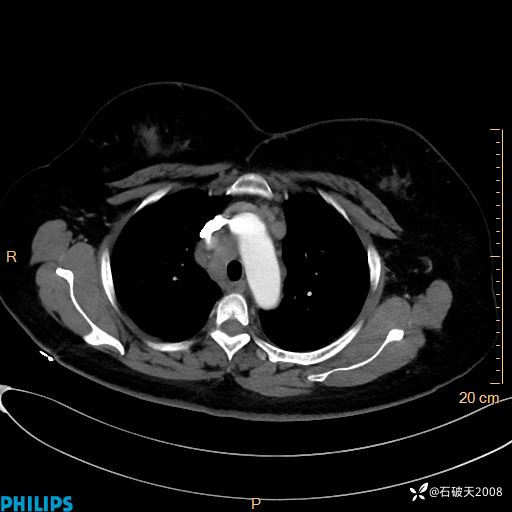

静脉期